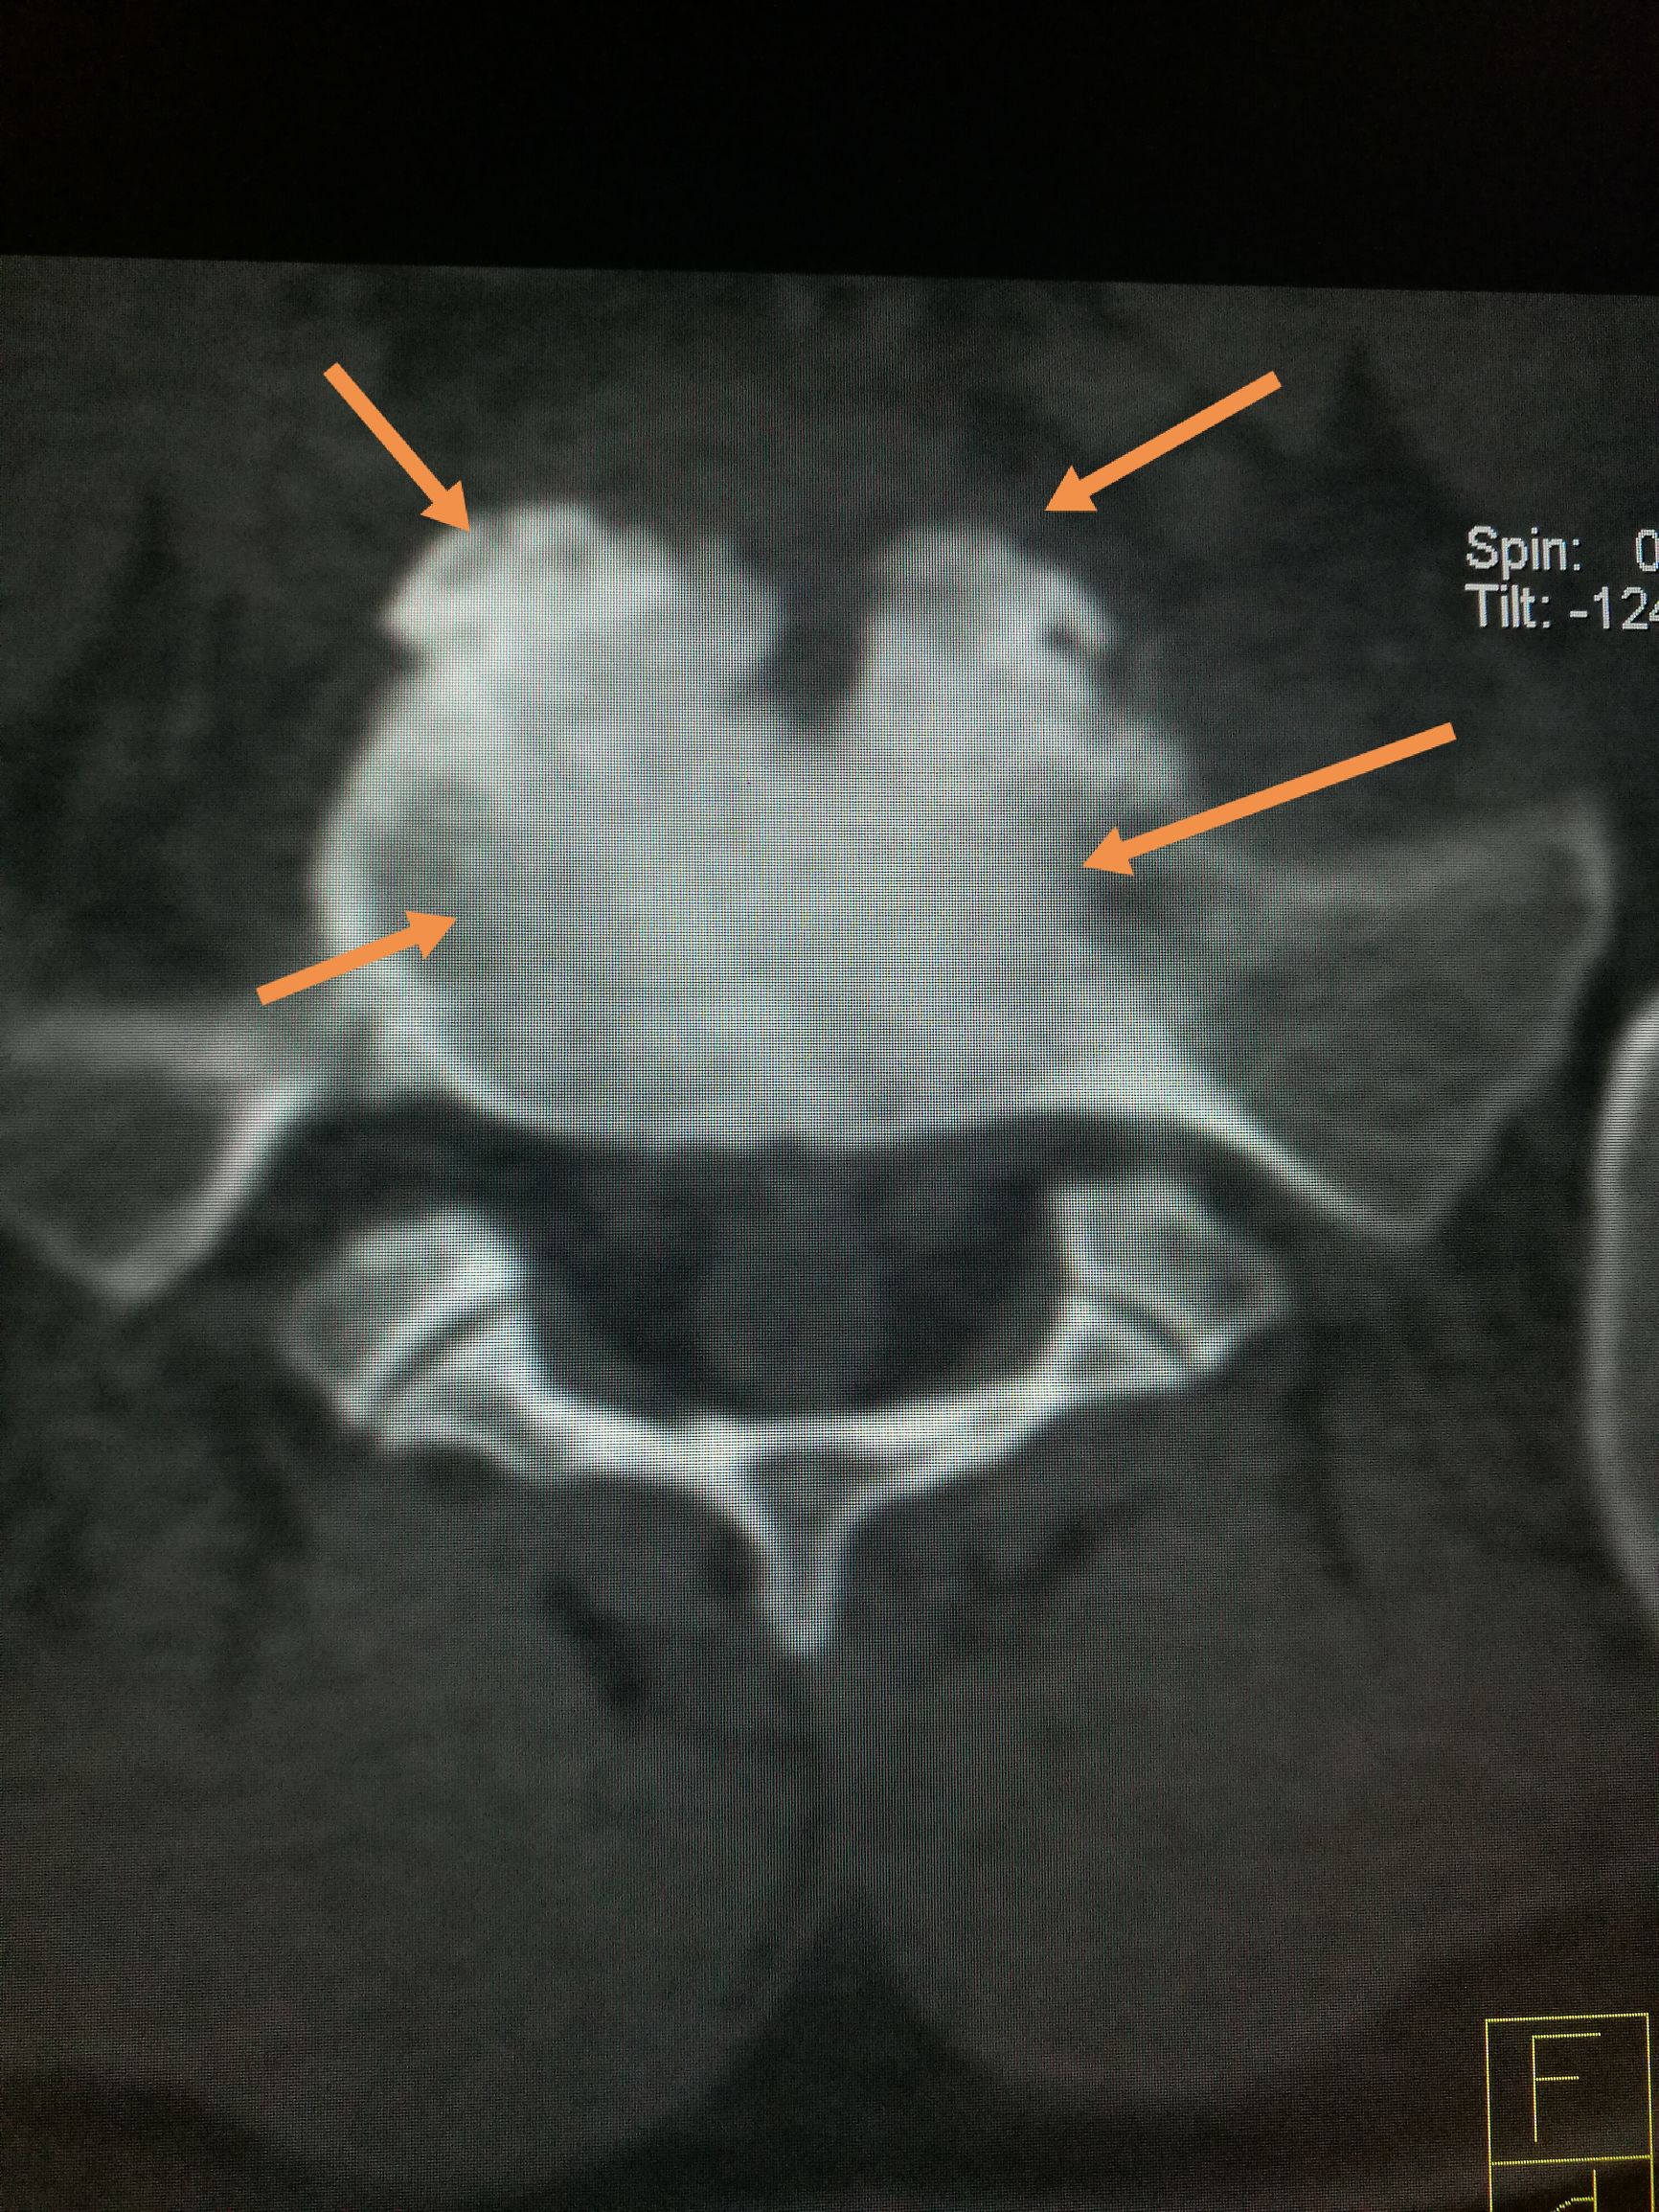

常吃牛羊肉,出现腰背痛,小心☞布鲁氏病 ​​​患者,男,22岁,以腰疼数月前来我处就诊,CT扫描可见第五腰椎下缘,骶椎上缘骨质破坏,骨密度增高,椎间隙未见明显狭窄,椎体旁未见软策划肿胀,未见异常包块,随后追问病史,主诉在*疆新**生活两年,后腰疼,在省防疫站查出来是布鲁氏杆菌感染,今来我处复查。